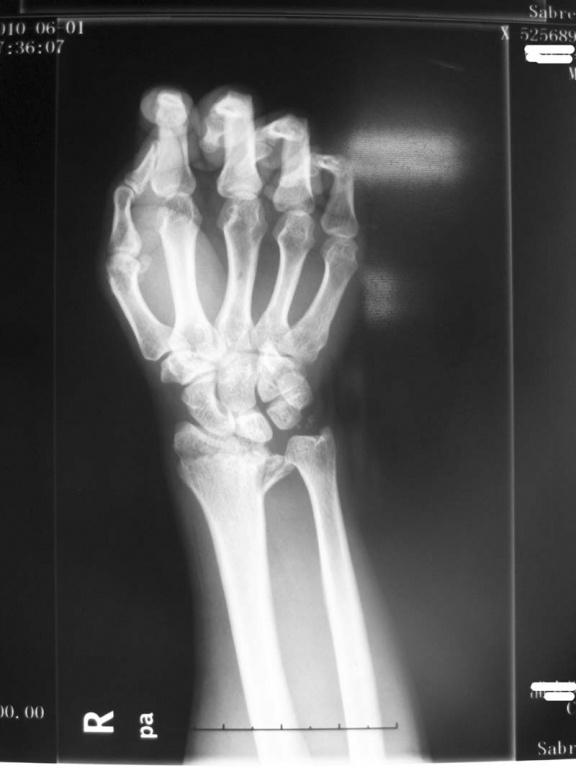

ct49984:右腕关节

左腕ct可见骨折粉碎移位严重.数条骨折线通过关节面.

因"高处坠落伤致右手腕疼痛,活动障碍1小时"住院.